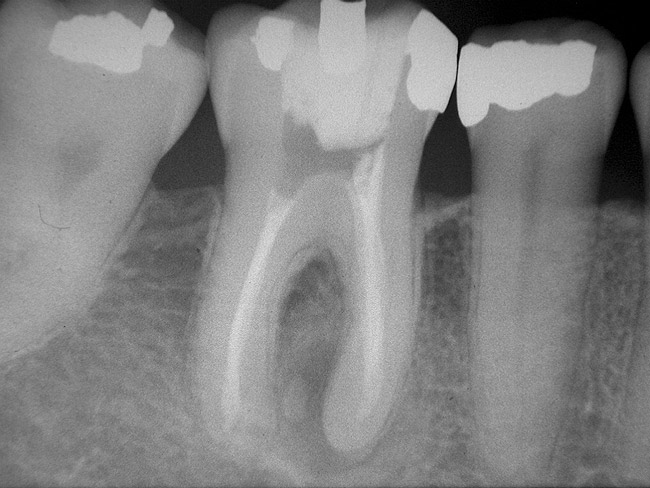

Figure 4a  Tooth No. 30 Nonsurgical root canal treatment had been completed 5 years before. The periapical radiograph revealed periradicular radiolucencies (periapical and in the furcation area).

Figure 4a

Figure 4b  The patient was asymptomatic, and periodontal probing depths were within normal limits; however, a new crown restoration was planned. Nonsurgical endodontic re-treatment was initiated. The intracoronal picture shows the previously treated 4 canals with infected gutta-percha filling.

Figure 4b

Figure 4c  Under high magnification, a furcation canal (Figure 4C) and a third distal canal (Figure 4D) were located.

Figure 4c

Figure 4d  Under high magnification, a furcation canal (Figure 4C) and a third distal canal (Figure 4D) were located.

Figure 4d

Figure 4e  The postoperative radiograph shows the re-treated tooth with 5 main canals.

Figure 4e

Figure 4f  The 1-year recall radiograph demonstrates the complete resolution of the periradicular radiolucencies.

Figure 4f